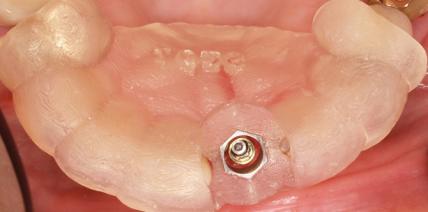

Erhalt einer Teilprothese mit Guided Surgery und Syncone